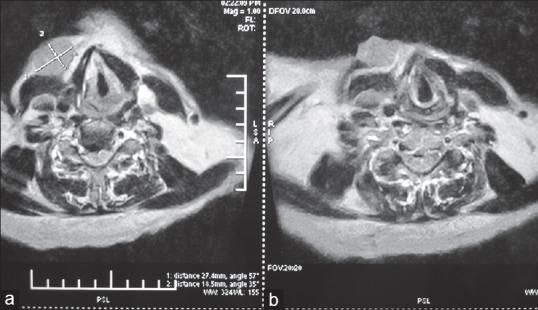

Ulcerative cutaneous nodule as a presenting feature of recurrent thyroid carcinoma.

Indian J Dermatol. 2014 Nov;59(6):616-8. doi: 10.4103/0019-5154.143545.